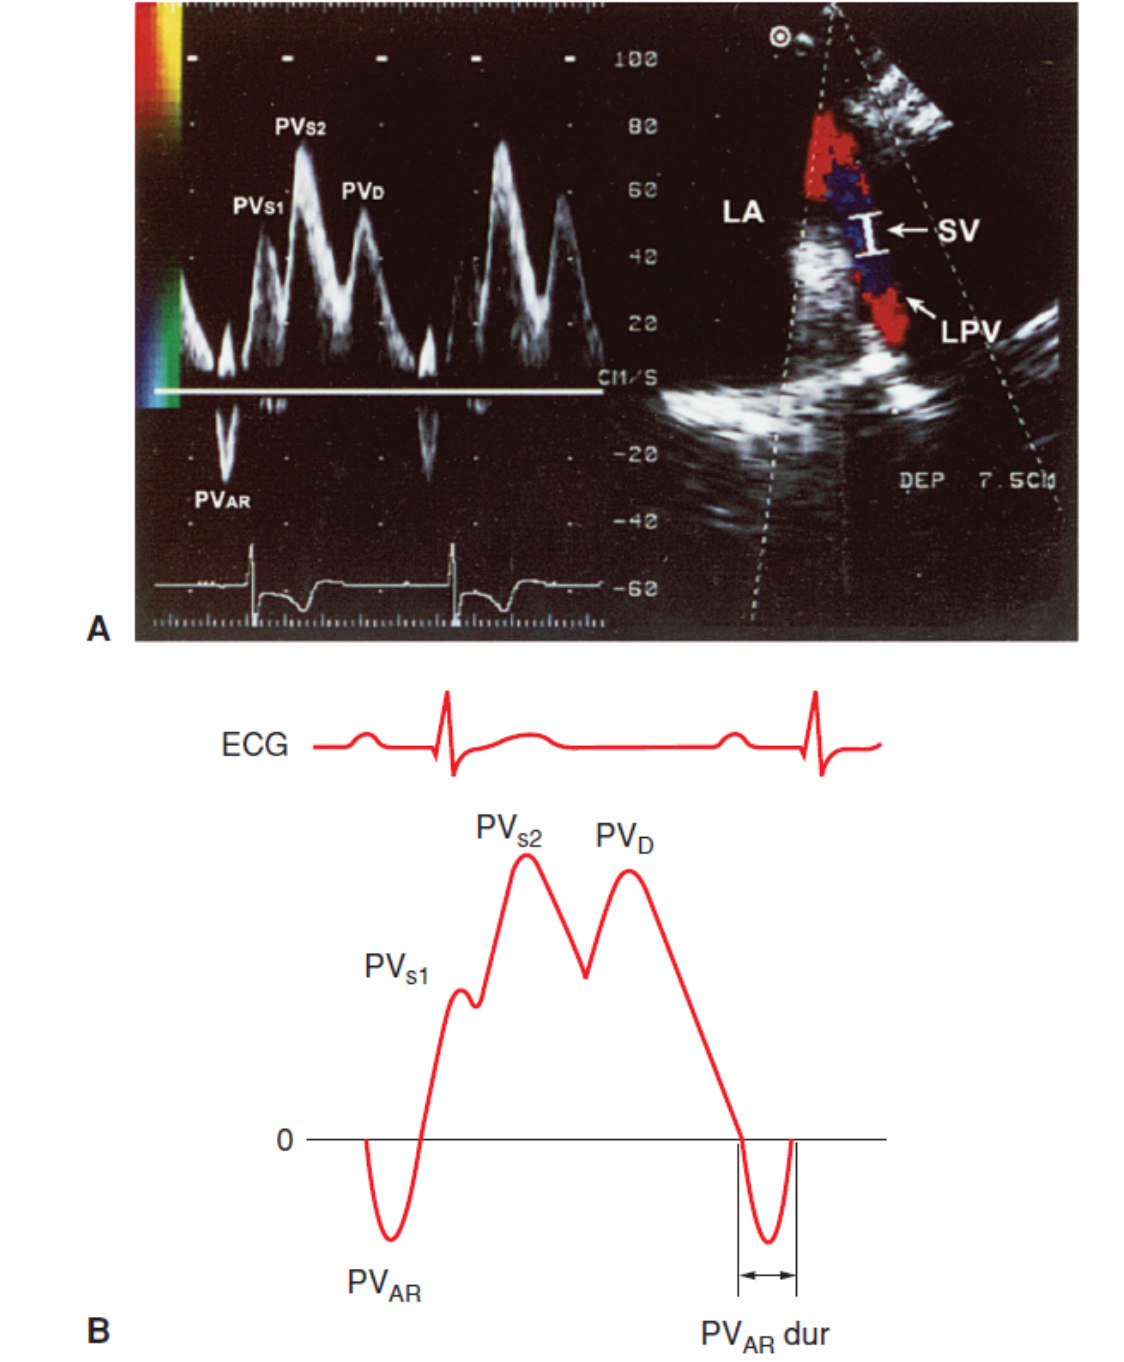

Explain the parts of the pulmonary vein waveform.

S1 - Atrial relaxation

S2 - Descent of ventricular base “sucks” blood into atrium

D: blood passively flows into atrium during ventricular diastole

A: Reversal wave - reflux when atria contracts

What is a typical pulmonary venous doppler flow profile?

antegrade systolic velocity which may be monophasic or biphasic ( PVs1, PVs2)

This is followed by an antegrade diastolic flow while mitral valve is open.

Finally a late diastolic flow reversal PVar

What A reversal wave velocity suggests elevated LVEDP?

Velocity > 35 cm/s

What is a normal pulmonary venous diastolic atrial flow reversal duration?

90-115 ms